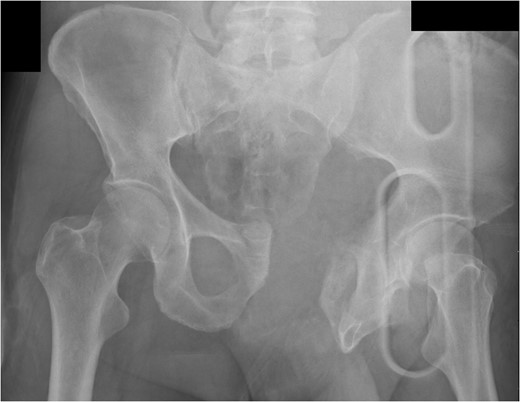

A 55-year-old male arrived at the ER, a large tree having fallen across his pelvis. The patient was hypotensive at the scene. He received over 1500 ml of crystalloid in route to the emergency room. Upon arrival to St. Mary’s Medical Center, the patient had a systolic pressure of 70. His heart rate was in the 130 s. The patient was awake and alert. A left subclavian central line was placed and he was transfused with two units of O-blood. The patient’s abdomen was soft and nontender. The patient had blood at his meatus. The patient’s pelvis was tender to palpation. His left leg was cold, mottled and pulseless. There was no femoral pulse on the left side. The chest x-ray was normal, however, the pelvis film revealed extreme widening and displacement of the symphysis pubis (Fig. 1). A bedsheet was wrapped around the patient’s pelvis and another two units of O-packed red blood cells were administered. Additionally, he was given four units of fresh frozen plasma. The patient was started on norepinephrine to control his persistent hypotension. His systolic blood pressure rose into the mid-90s and the patient was taken to the CT scanner. The CT scan revealed that the patient had an acute occlusion of his left iliac artery, as well as a large left iliac wing fracture with a massive associated hematoma. A right iliac wing fracture was located near the sacroiliac joint. There was pubic diastasis, as well as a left superior rami fracture with a modest associated hematoma. There was no extravasation of dye (Figs 2 and 3). The patient was taken directly to the operating room because he was developing significant abdominal distention in the face of continued hypotension. Anesthesiologists placed a second large-bore central line for fluid resuscitation. An exploratory laparotomy was performed, revealing an intraperitoneal bladder rupture. The patient was bleeding freely from his pelvic hematoma. Multiple attempts were made to pack the pelvis tightly with laparotomy pads, but efforts were unsuccessful. Because of the distorted anatomy obtaining proximal and distal control of the iliacs was extremely difficult. The patient suffered massive retroperitoneal venous bleeding, which we were unable to control. The patient exsanguinated on the operating room table; despite having received over 30 units of packed red blood cells, 30 units of fresh frozen plasma, several 10 packs of platelets, cryoprecipitate and factor VII A.